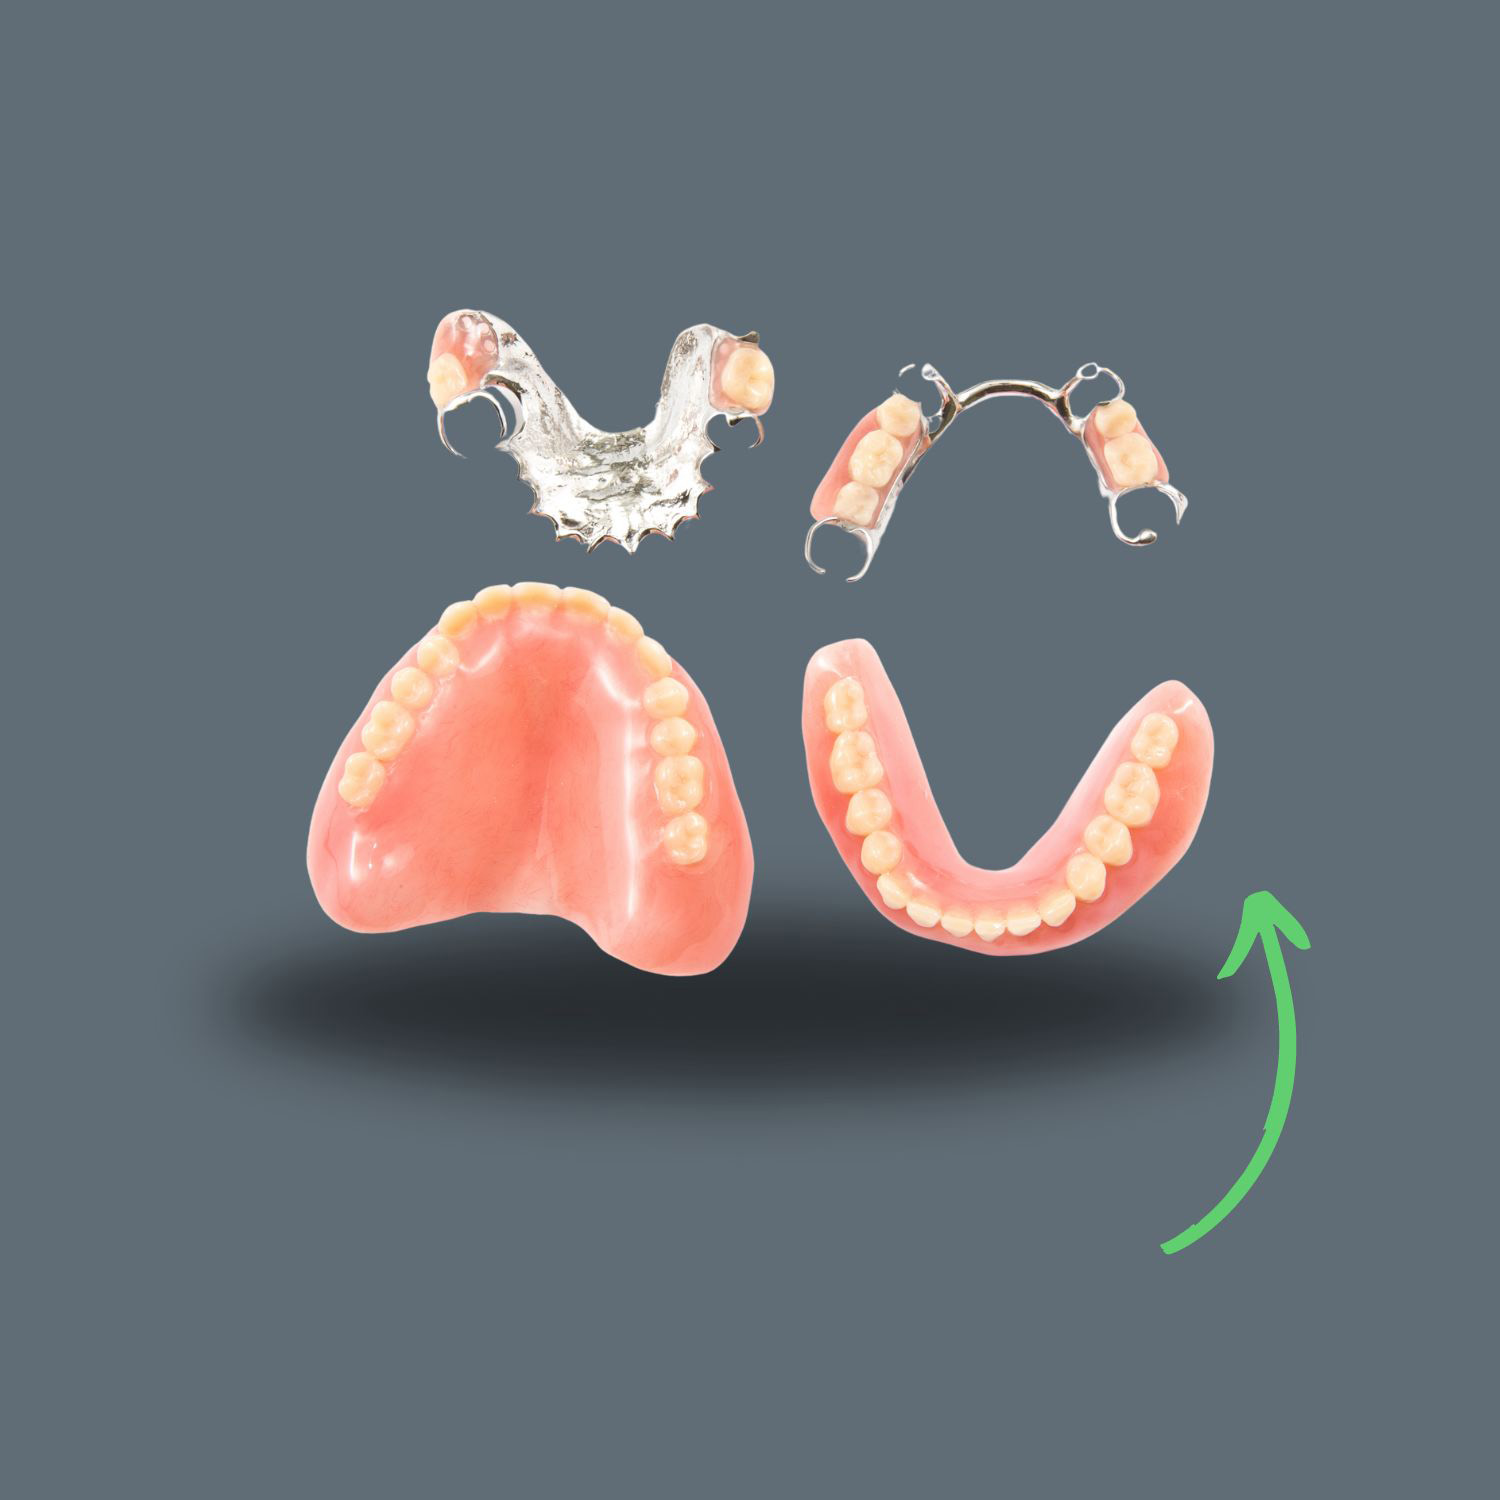

Частичната подвижна протеза е подвижна зъбна протеза, която замества множество зъби и загубените меки тъкани в денталния дъга на горната или долната челюст.

Съществуват различни видове частични подвижни протези:

– Хромови частични подвижни протези: Основно се състоят от метална рамка, направена от сплав на тези два метала, към която са прикрепени розов акрил и акрилни зъби. Кобалт-хромовите протези могат да бъдат изработени много тънки, затова са много по-малко обемни от акриловите протези и в повечето случаи небцето може да остане открито вместо да бъде покрито от протезите.